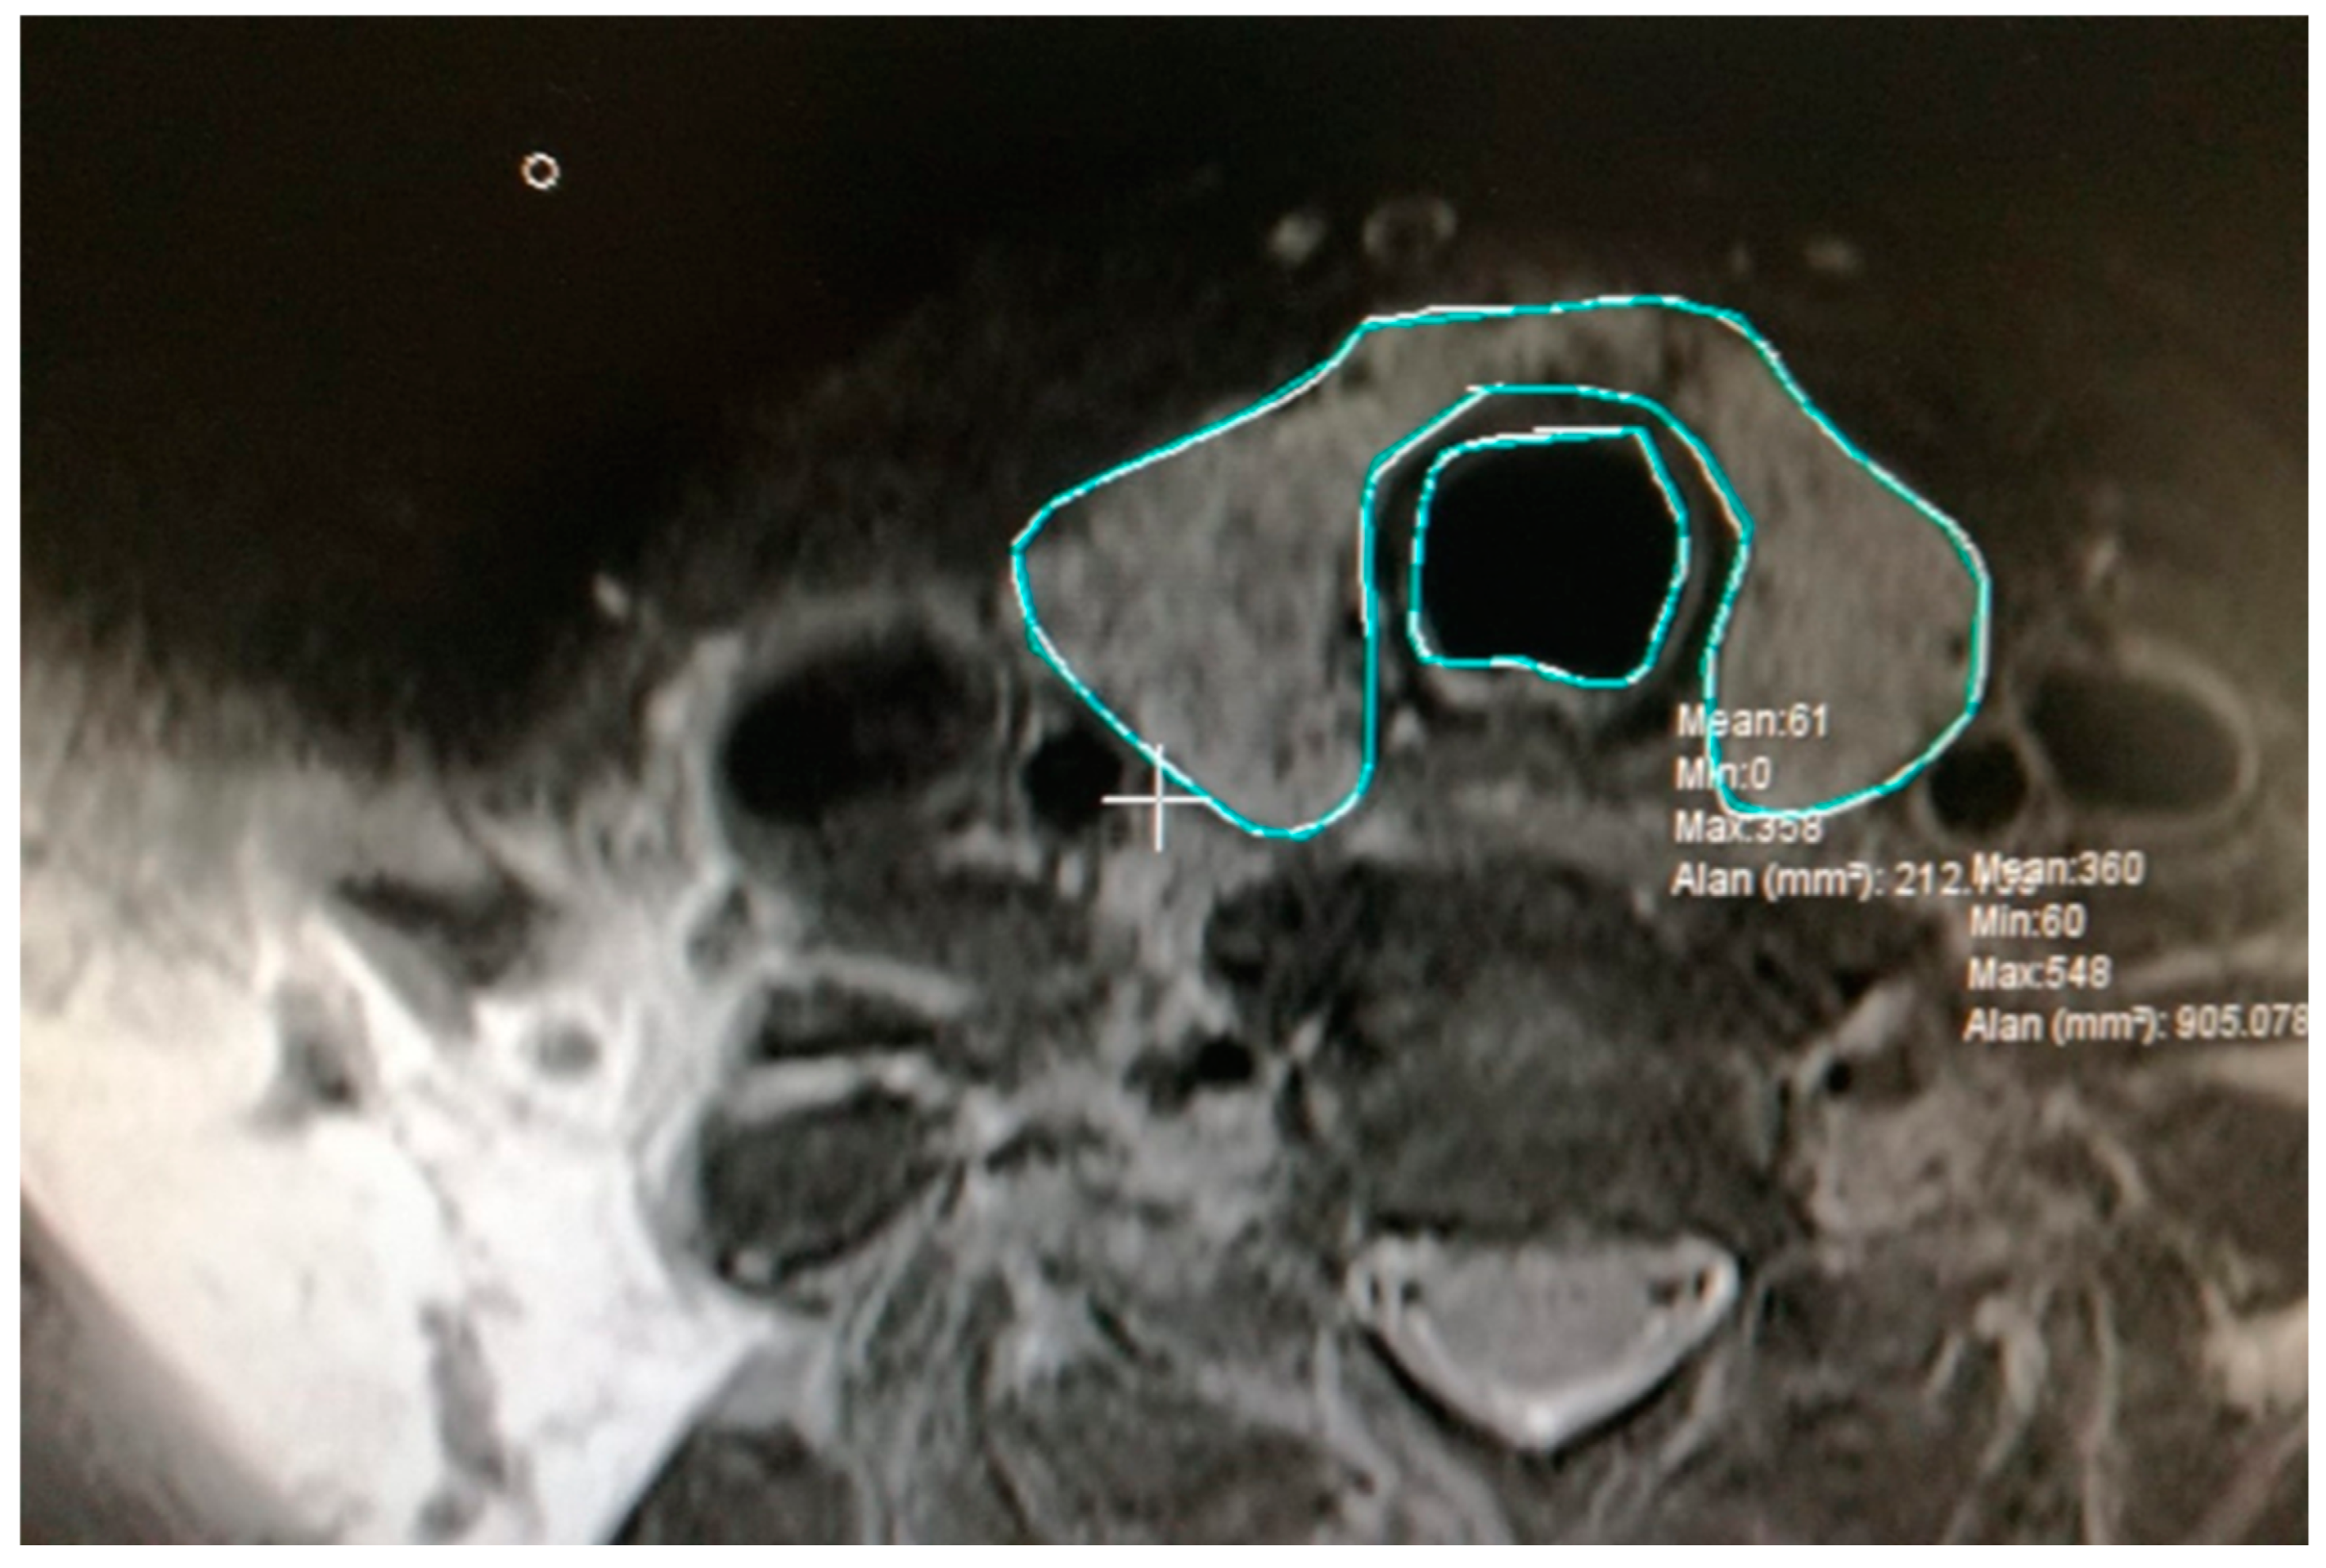

2.2. Calculation of Total Volume of Thyroid and Trachea

| Volume | Minimum Volume (µm3) | Maximum Volume (µm3) | Mean Volume (µm3) |

|---|---|---|---|

| Pre-RAI Thyroid volume | 59,625,000,000 | 586,440,000,000 | 331,940,725,000 |

| Post-RAI Thyroid volume | 67,612,500,000 | 571,275,000,000 | 216,330,725,000 |

| Pre-RAI Trachea volume | 16,920,000,000 | 71,662,500,000 | 42,768,375,000 |

| Post-RAI Trachea volume | 17,010,000,000 | 99,450,000,000 | 48,594,875,000 |